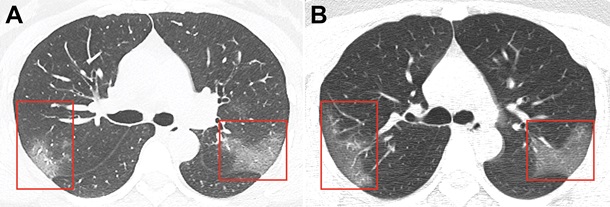

Снимки были получены в результате компьютерной томографии 33-летней женщины, госпитализированной в китайском городе Ланьчжоу с температурой 39 градусов.

Снимки были сделаны с разницей в три дня. На первом из них в нижней доле уже заметны зоны поражения инфекцией - они похожи на большие светлые области. На снимке, сделанном спустя три дня уже заметно, что зона поражения расширяется.